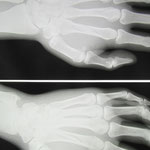

●右第3中手骨骨折

中学2年生 ラクビープレー中に骨折をしました。

当初、整形外科の診察を受けギプス固定をしてもらいましたが、

ボクシンググローブのような大きなもので、しかもギプスが皮膚を圧迫していたので当院に相談されました。

3週間後には大事な試合が待っています。

提携の整形外科で再度レントゲン検査をしてもらい転移(骨のずれ)がないことを確認し小さな固定にかえました。

毎日来院してもらい超音波治療とマッサージをしました。

2週経過した頃から圧痛(折れたところを押したときの痛み)は消失し、なんとか試合に間に合いました。

念のためさらに1週間来院してもらい治療を終了しました。